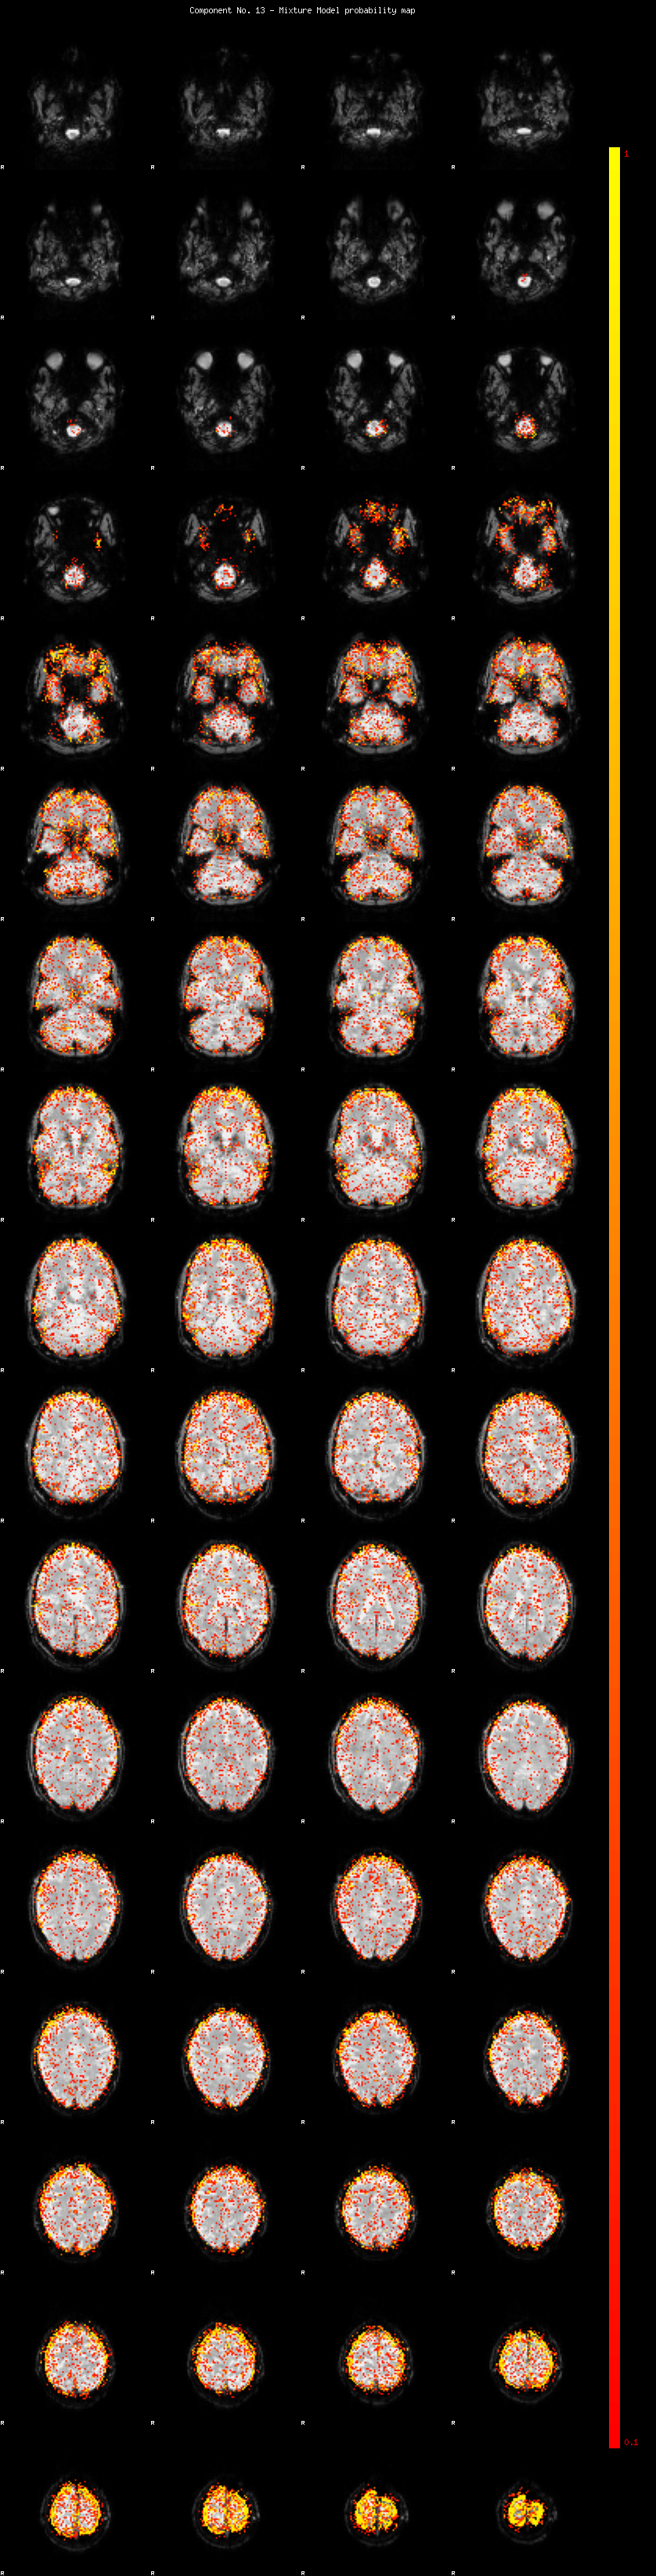

IC_13 Mixture Model fit

Means : -0.000000 2.924462 -2.549399

Vars : 1.000000 3.427930 1.383626

Prop. : 0.891974 0.069727 0.038298